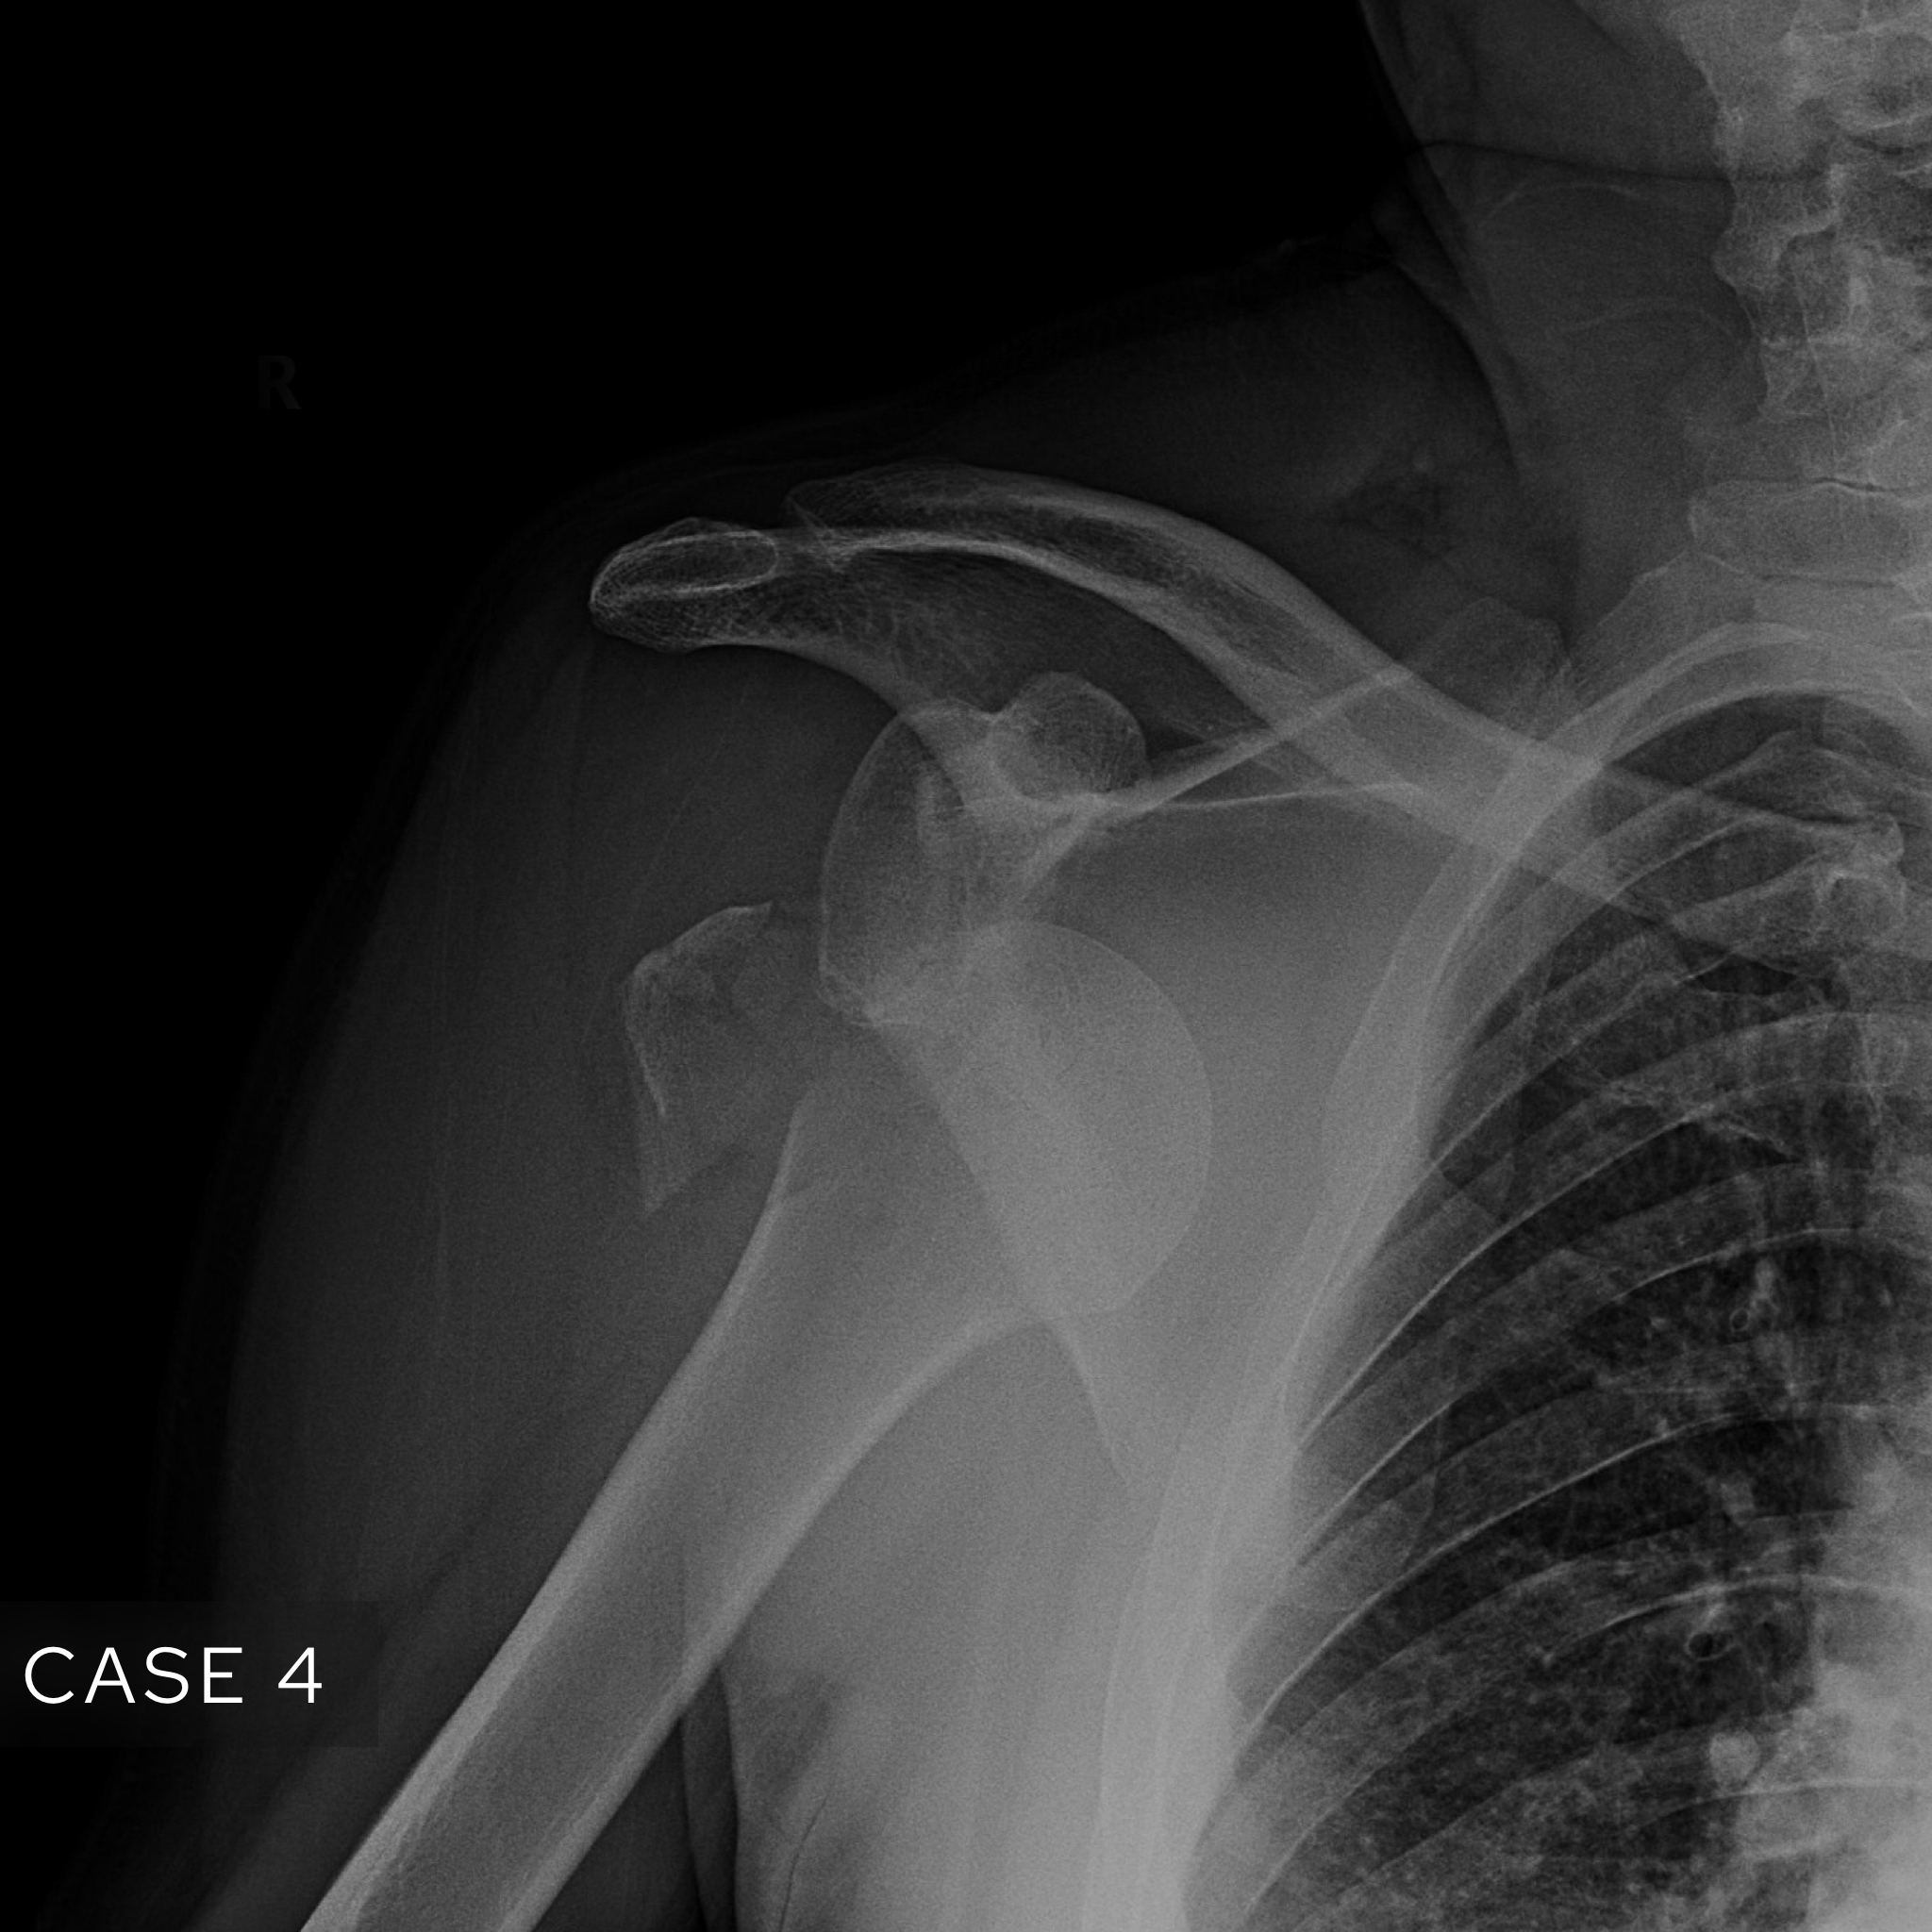

Case 3

A male in his 80s presents to the Emergency Department with shoulder pain and deformity after an episode of trauma. What is the diagnosis?

Choose from one of the following options: